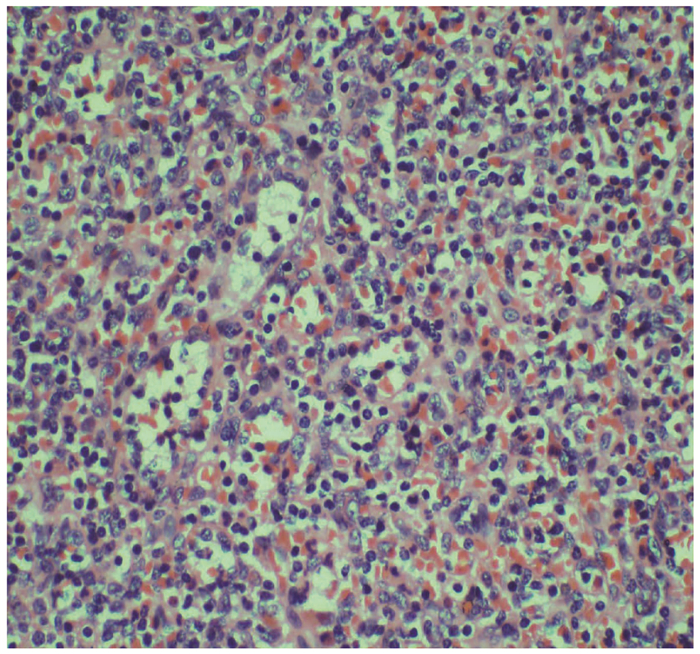

Intrapancreatic accessory spleen misdiagnosed as pancreatic neuroendocrine tumor: A case report

Xuxiang XIA, Guoyue LYU, Xiaotong QIU, Wei QIU

2022, 38(2): 436-438. DOI: 10.3969/j.issn.1001-5256.2022.02.036

Abstract(1098) HTML (844) PDF (2885KB)(44)

Abstract: